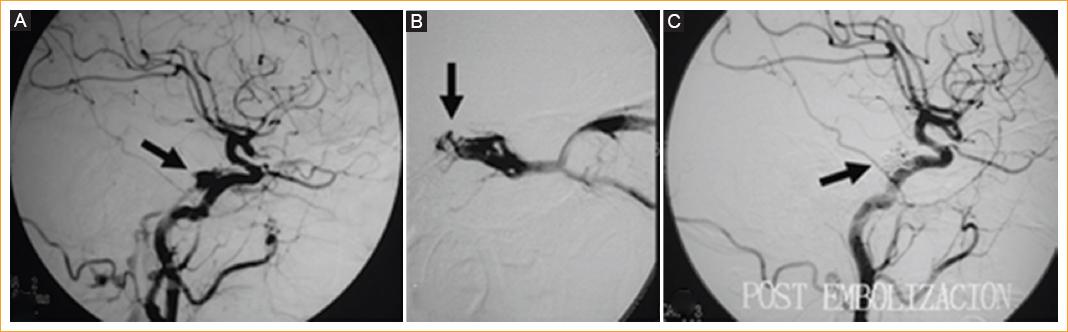

Tras estos hallazgos se realiza una angiografía cerebral para confirmar el diagnóstico (Fig. 4 A), en la que se demuestra una fístula carotidocavernosa de bajo flujo que, según la clasificación de Barrow3 (Fig. 3 C), es indirecta tipo B nutrida por ramas durales del tronco meningohipofisiario de la carótida interna izquierda (Fig. 4 A). Se procede entonces a realizar una embolización con coils por vía endovenosa, a través del seno petroso inferior, hasta llegar al seno cavernoso (Fig. 4 B). El control angiográfico final (Fig. 4 C) muestra la completa oclusión de la fístula por los coils.

Figura 4 Angiografía cerebral. A: fístula carotidocavernosa de bajo flujo (flecha) nutrida por ramas durales del tronco meningohipofisiario de la carótida interna izquierda (Barrow tipo B). B: embolización con coils por vía venosa, a través del seno petroso inferior hasta el seno cavernoso. C: control angiográfico posterior a la embolización que muestra la completa oclusión de la fístula por los coils.